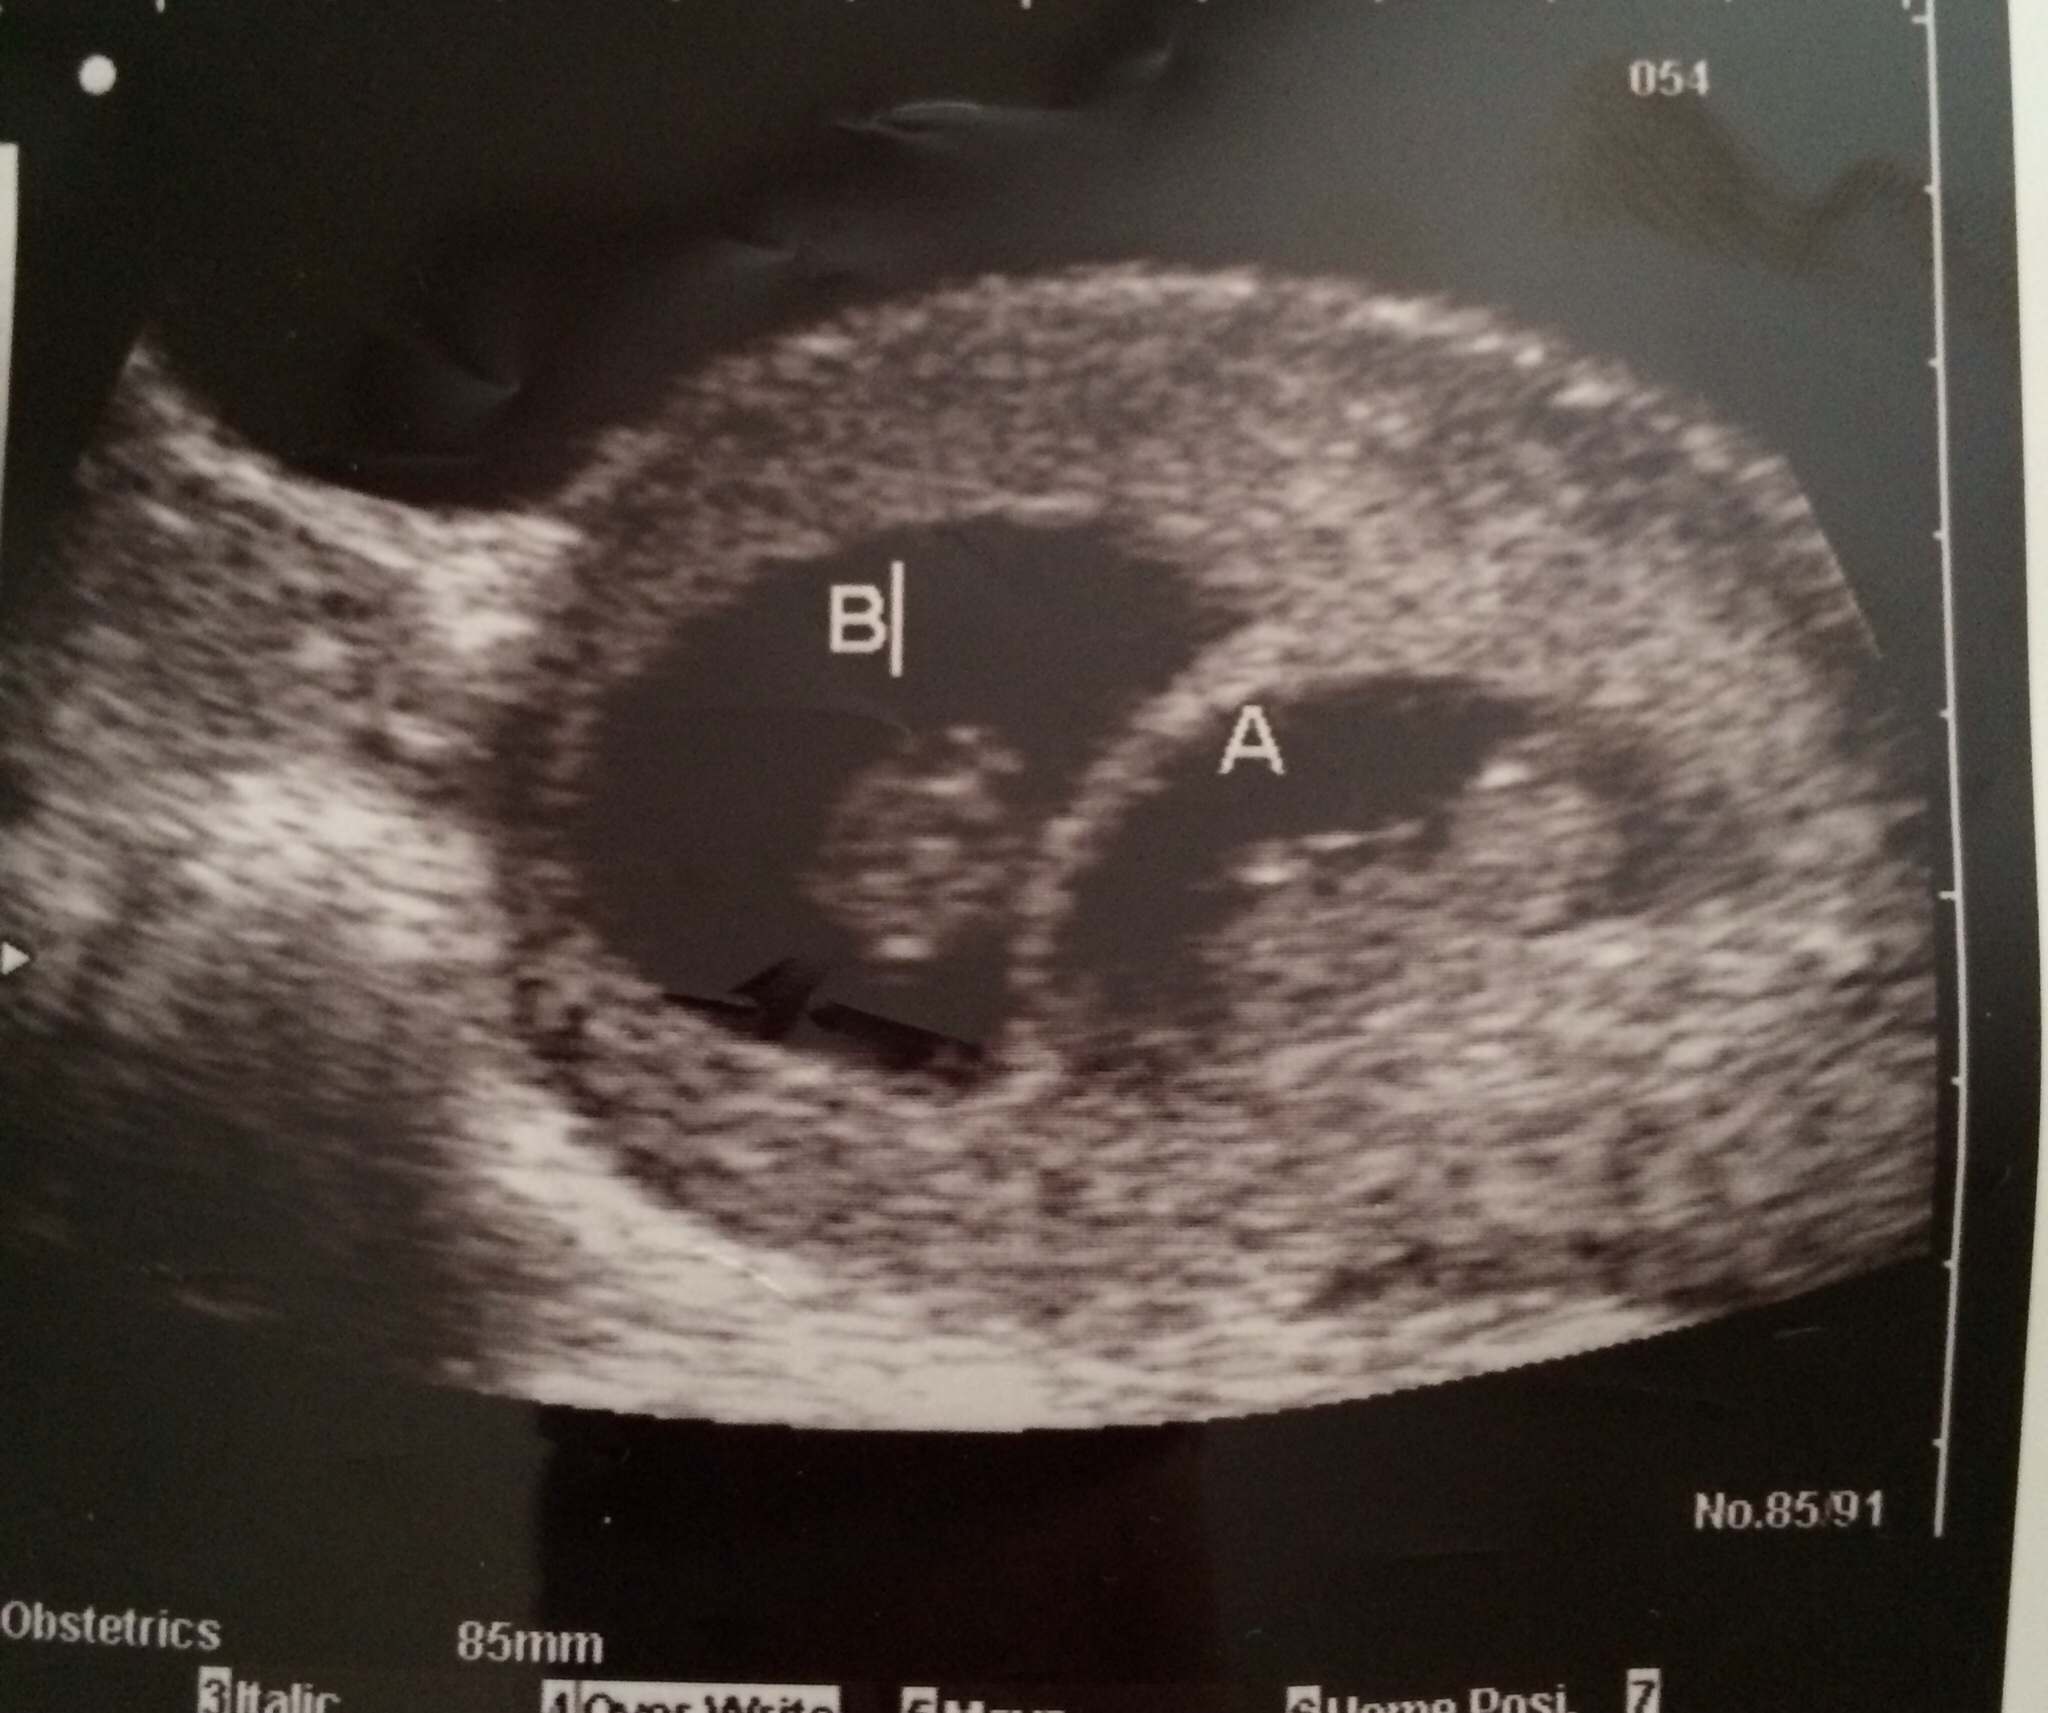

Here is our second ultrasound! 8w0d to check on twins. Unfortunately we lost our second baby. On a good note, we have one strong healthy baby with a heartbeat of 178!!

heres my new one on the left... and compared to my daughter who is now 2.5 yo on the right... im trying to use the Ramzi method to figure out gender now...